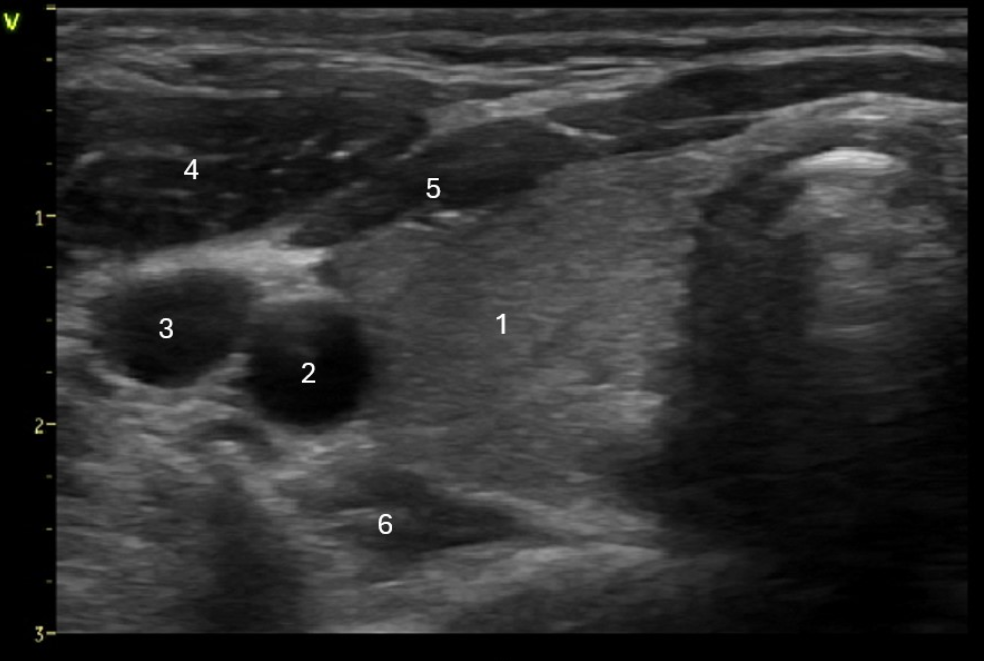

Which of the following structures is labeled #6?

A. Longus Colli muscle

Right lobe of the thyroid

Right carotid artery

Right internal jugular vein

Sternocleidomastoid muscle

Strap muscles

Longus colli muscle

Which muscle group is located posterior to the thyroid gland?

C. longus colli muscle

Strap muscles are anteromedial to the gland. Sternocleidomastoid muscles are anterolateral to the gland. Longus Colli muscles are posterior to the thyroid lobes.

Locate the common carotid artery

The common carotid artery is lateral to the thyroid gland. The internal jugular vein is slightly anterior and lateral to the common carotid artery.

Find the internal jugular vein